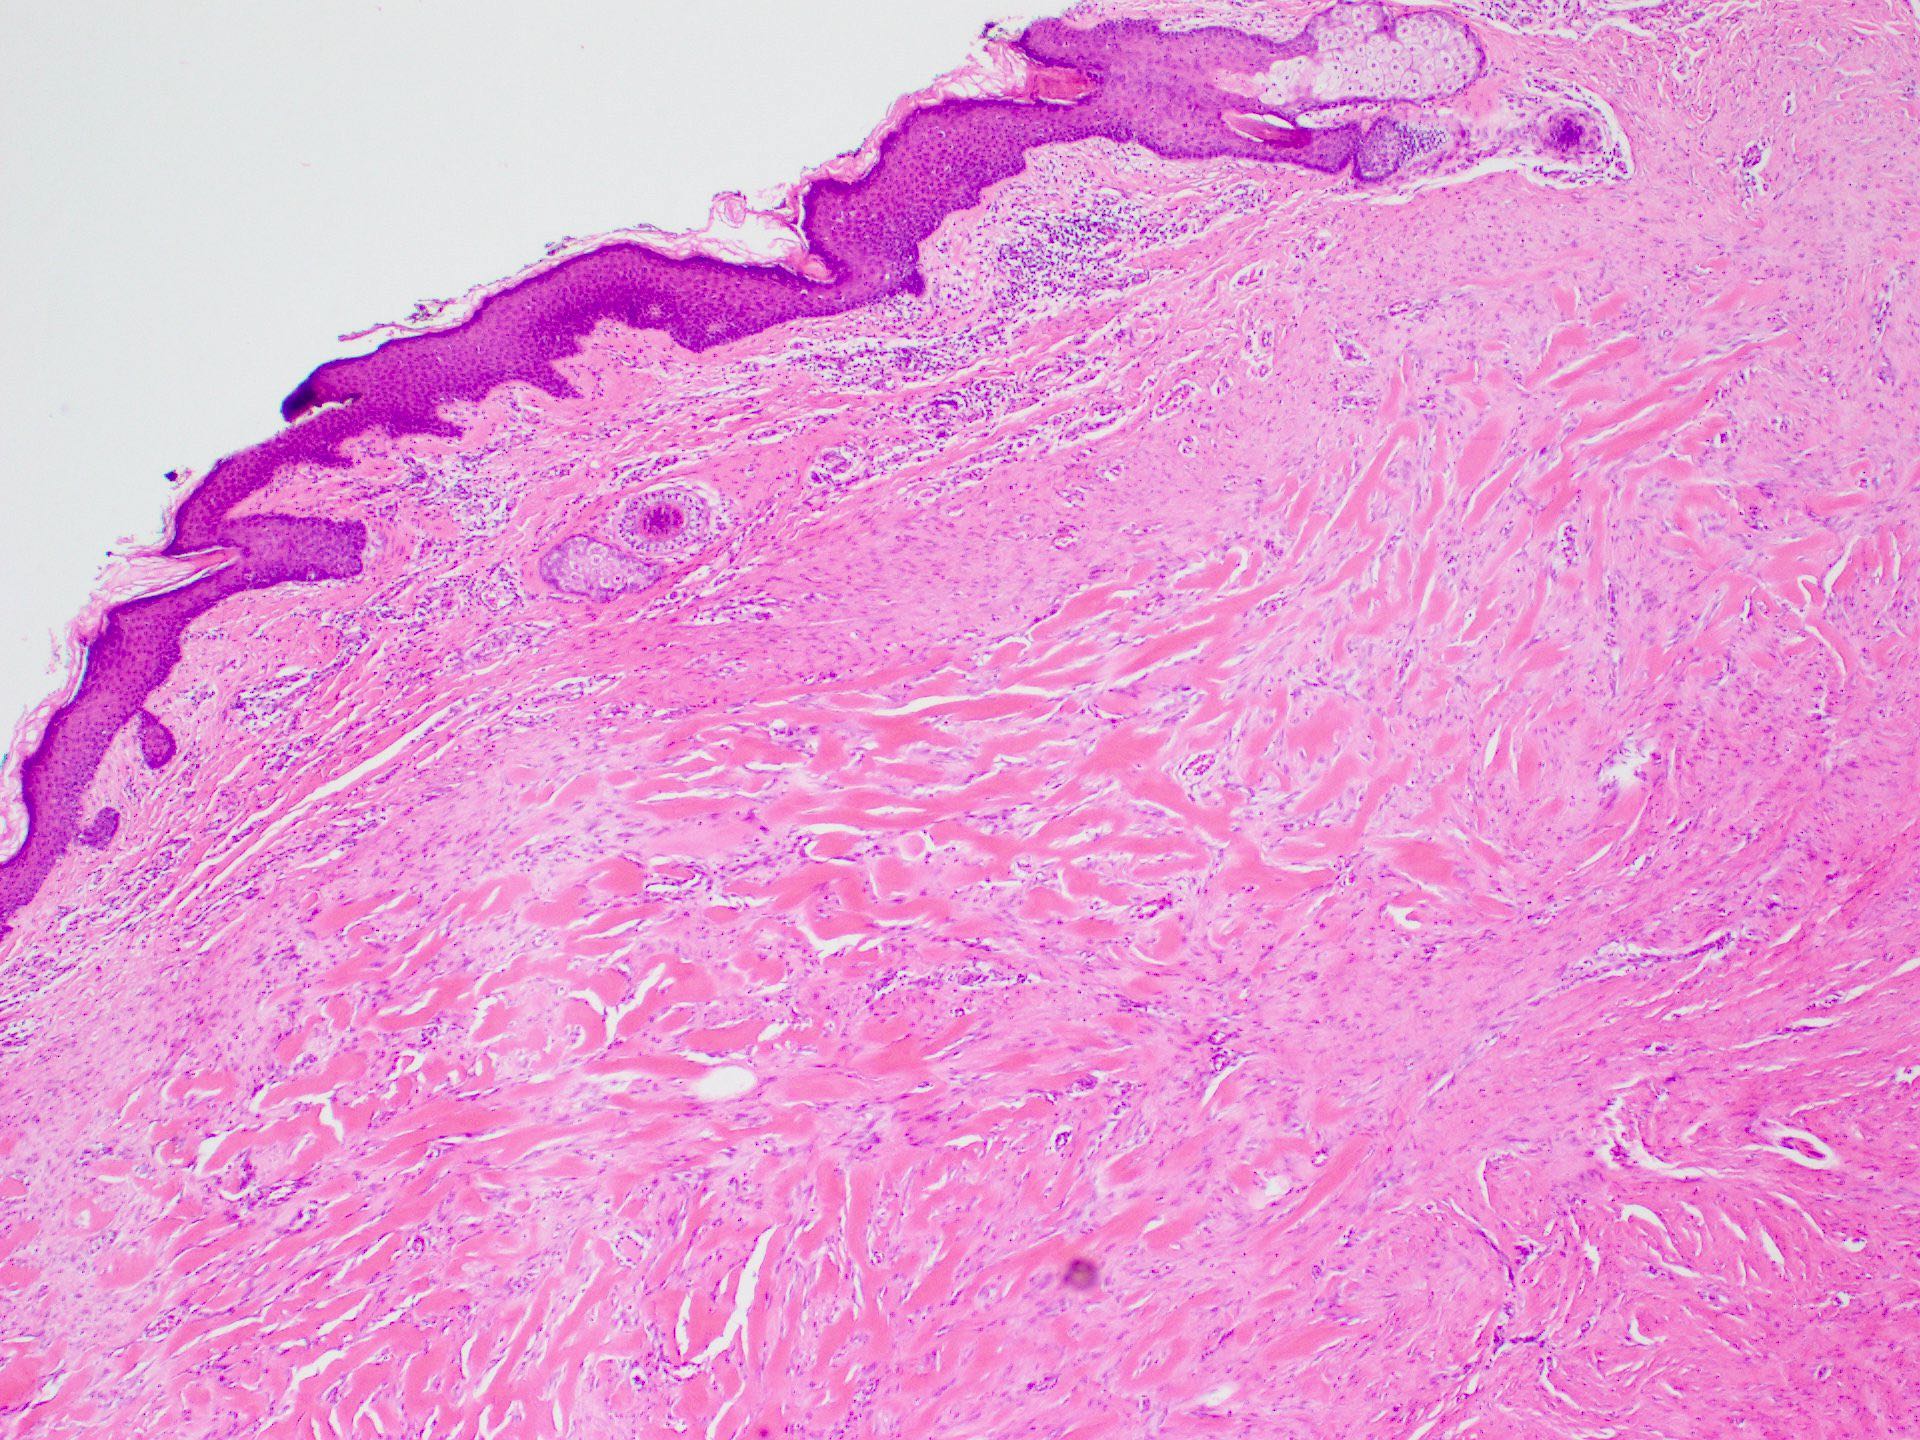

Microscopic (histologic) description

- Lesion of the deep dermis; sparing of papillary dermis (Am J Dermatopathol 2004;26:379)

- Characteristic long, broad, closely packed collagen bundles that stain uniformly eosinophilic (keloidal collagen) arranged in haphazard fascicles (Scars Burn Heal 2021;7:2059513120980320)

- Tongue-like advancing edge (Front Cell Dev Biol 2020;8:360)

- Epidermis may be normal, thin or thick (most) and may be affected by secondary changes (such as hypertrophy and inflammation due to irritation / scratching) (Front Cell Dev Biol 2020;8:360)

- Lesion replaces adnexal structures (i.e., hair follicles and sweat glands) (Histol Histopathol 2015;30:1033)

- Tend to have marked inflammation in the dermis at the leading edge of growing keloids (Scars Burn Heal 2021;7:2059513120980320)

Microscopic (histologic) images